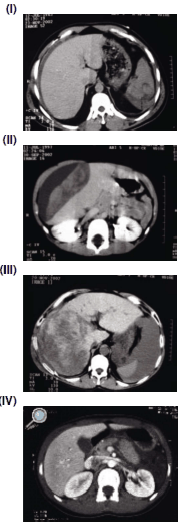

Relacione as imagens de tomografia computadorizada pós-trauma abdominal, na coluna da esquerda, com o seu respectivo diagnóstico, na coluna da direita.

(A) Lesão hepática grau V.

(B) Lesão esplênica.

(C) Ruptura pancreática.

(D) Lesão hepática grau III.

Assinale a alternativa que contém a associação correta.